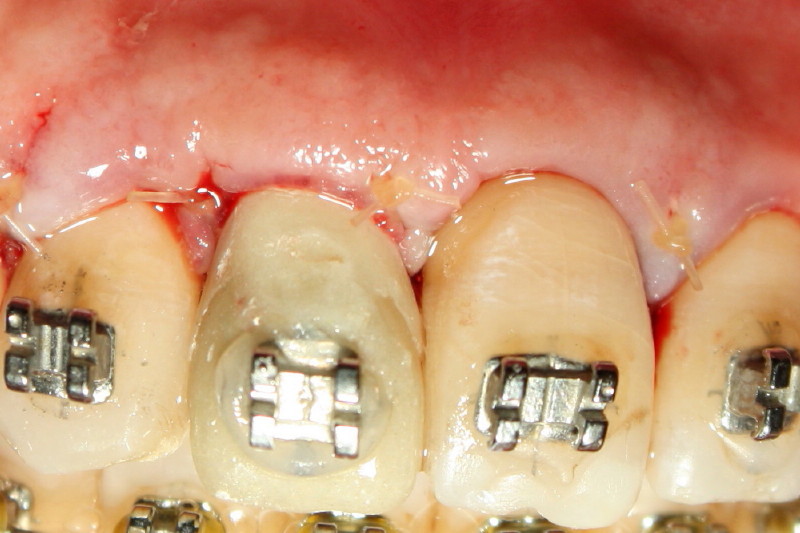

Fig.5. After further trimming of the temporary crown to create gingival embrasure and removal of minimal crest bone, the crown is cemented. The flap is sutured. Return to main article